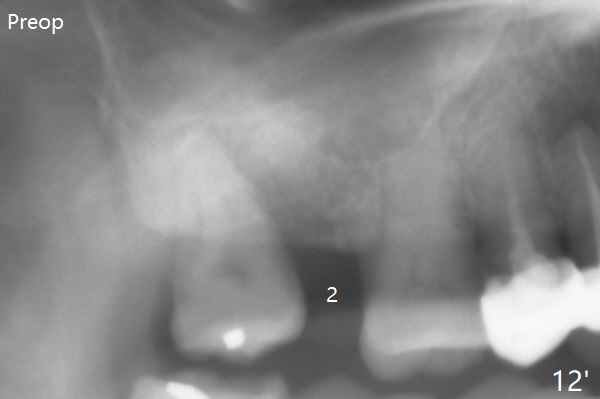

The distal cortical bone contacts the implant (Fig.12 ^), while the mesial bone increases in density (*) 2 years postop, as compared to Fig.12' (preop).